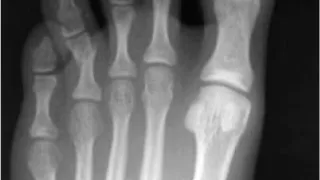

午前の病院での仕事と肋骨骨折と足趾開放骨折の急患今朝は曇り空のスタートでしたが, 雲の切れ間から青空がのぞきました。季節の変わり目らしい, 少しヒンヤリした空気の中, いつものように出勤しました. 8時から後輩医師とともに朝の病棟回診を行い...